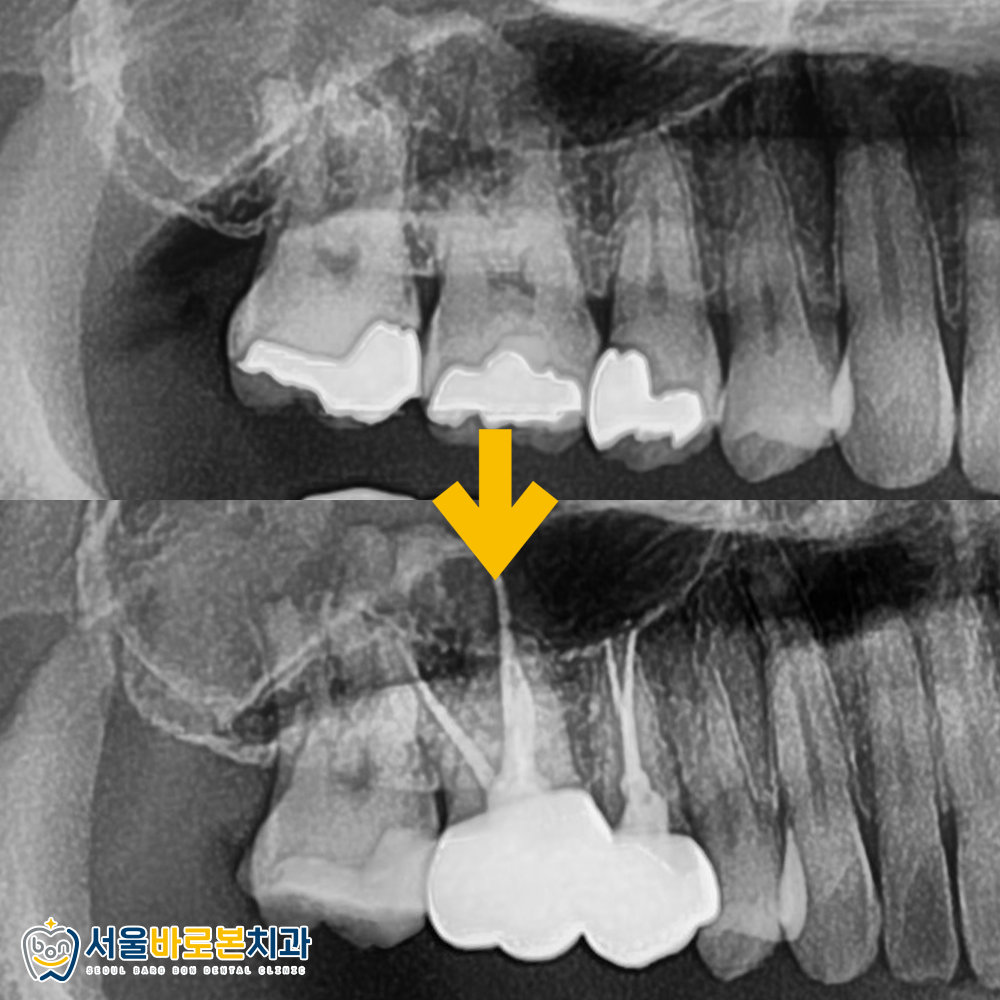

방사선 사진상에서도

확실하게 확인이 됩니다.

때워져 있던 금 인레이 아래로

2차 충치가 진행되고 있었는데요.

기존에 수복되어 있던

오래된 골드 인레이를 모두 제거해 보고 나니,

내부가 아주 심하게 상해 있었습니다.

그래서 2개 치아는 신경치료,

나머지 1개 치아는 인레이로 결정했습니다.

앞 쪽의 두 치아는 신경치료를 진행했습니다.

치아 내부가 심하게 오염되어

썩어 있던 부분과 신경을 깨끗하게 제거하고

뿌리 끝까지 치과 재료를 통해 밀봉하고,

크라운 제작을 위한 준비에 들어갔습니다.

보철물까지 씌워 마무리했습니다.